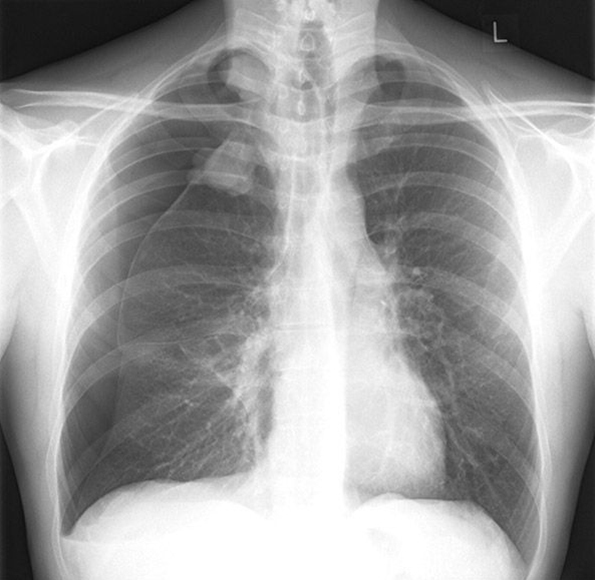

Une radio de thorax de face est réalisée.

Question 11 - Concernant cette radiographie du thorax quelle est la ou les proposition(s) vraie(s) ?

Il y a un pneumothorax droit sur cette radio, il est complet car le poumon est complètement décollé sur toute sa hauteur. La 1re côte donne souvent l’impression d’un pneumothorax apical par son arc antérieur, mais c’est un pur effet de contraste. Sur cette radio il n’y a pas de signe de gravité radiologique. Attention ! la déviation du médiastin (non présente ici) n’est pas un signe de gravité du pneumothorax. Il ne faut jamais faire de radio en expiration en cas de suspicion de pneumothorax, ça pourrait entraîner un collapsus par diminution du retour veineux. Le pneumothorax comprime la veine cave et diminue le retour veineux, l’expiration diminue encore plus ce retour veineux et peut entraîner un désamorçage de la pompe cardiaque. Le drainage se fait soit par voie antérieure en dehors de la ligne médio-claviculaire entre le 2e et le 3e EIC, soit par voie axillaire sur la ligne axillaire moyenne entre le 4e et le 5e EIC. Pour avoir un repère, retenir que le mamelon est au niveau du 5-6e EIC, donc on ne draine jamais en-dessous du mamelon.